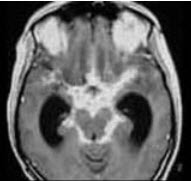

女患者,35岁,发热、头痛、呕吐3天,体重减轻,有肺结核史5年。查体颈抵抗感,克氏征(±)头颅MRI表现如图,最可能的诊断是( )

A:病毒性脑膜炎

B:隐球菌性脑膜炎

C:单纯疱疹病毒性脑炎

D:结核性脑膜炎

E:神经系统钩端螺旋体病